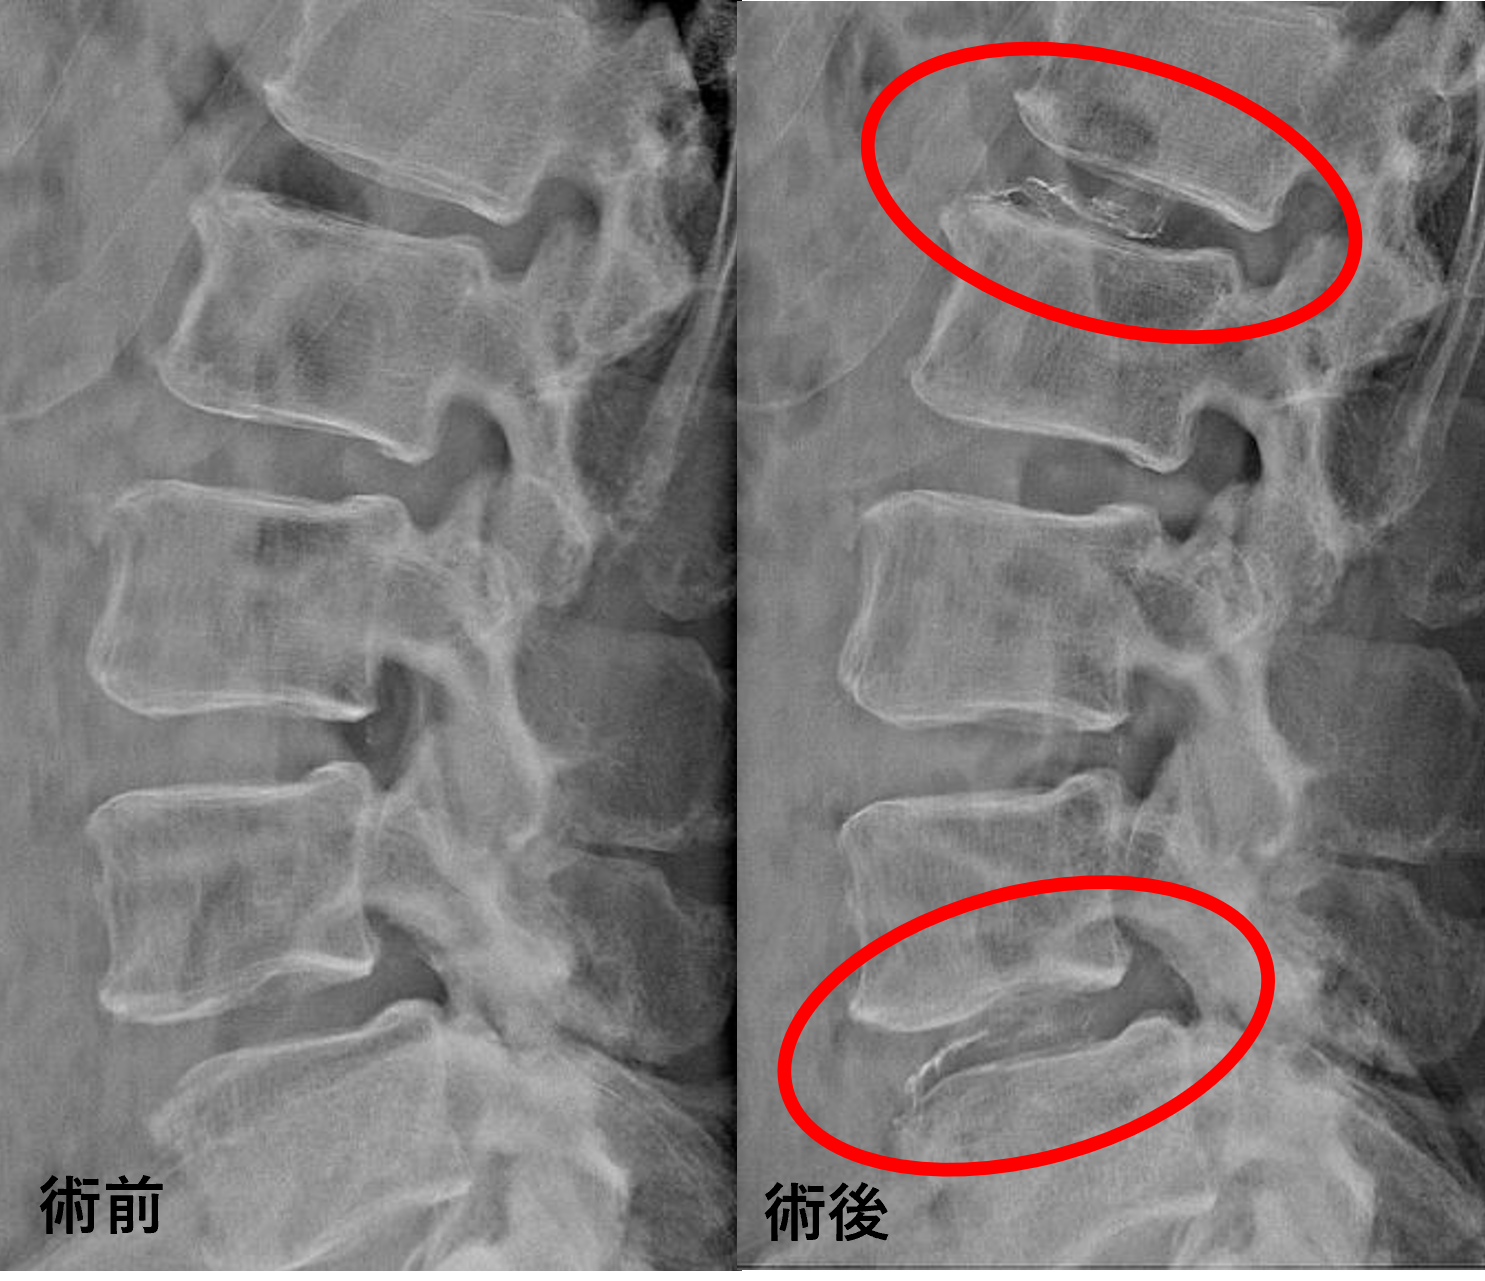

画像及び所見について

- L1/2 – 椎間板変性、膨隆、椎間孔狭窄

- L2/3、3/4、5/s – 軽度椎間板変性、軽度膨隆、軽度椎間孔狭窄

- L4/5 – 椎間板変性、膨隆、椎間孔狭窄、脊柱管狭窄、軽度前方変性すべり

以上のことが画像上認められました。

L1/2、4/5の椎間板所見による脊柱管の圧排が、症状の原因の可能性がもっとも高い。

患者様と相談の元、L1/2、4/5にセルゲル法を施行